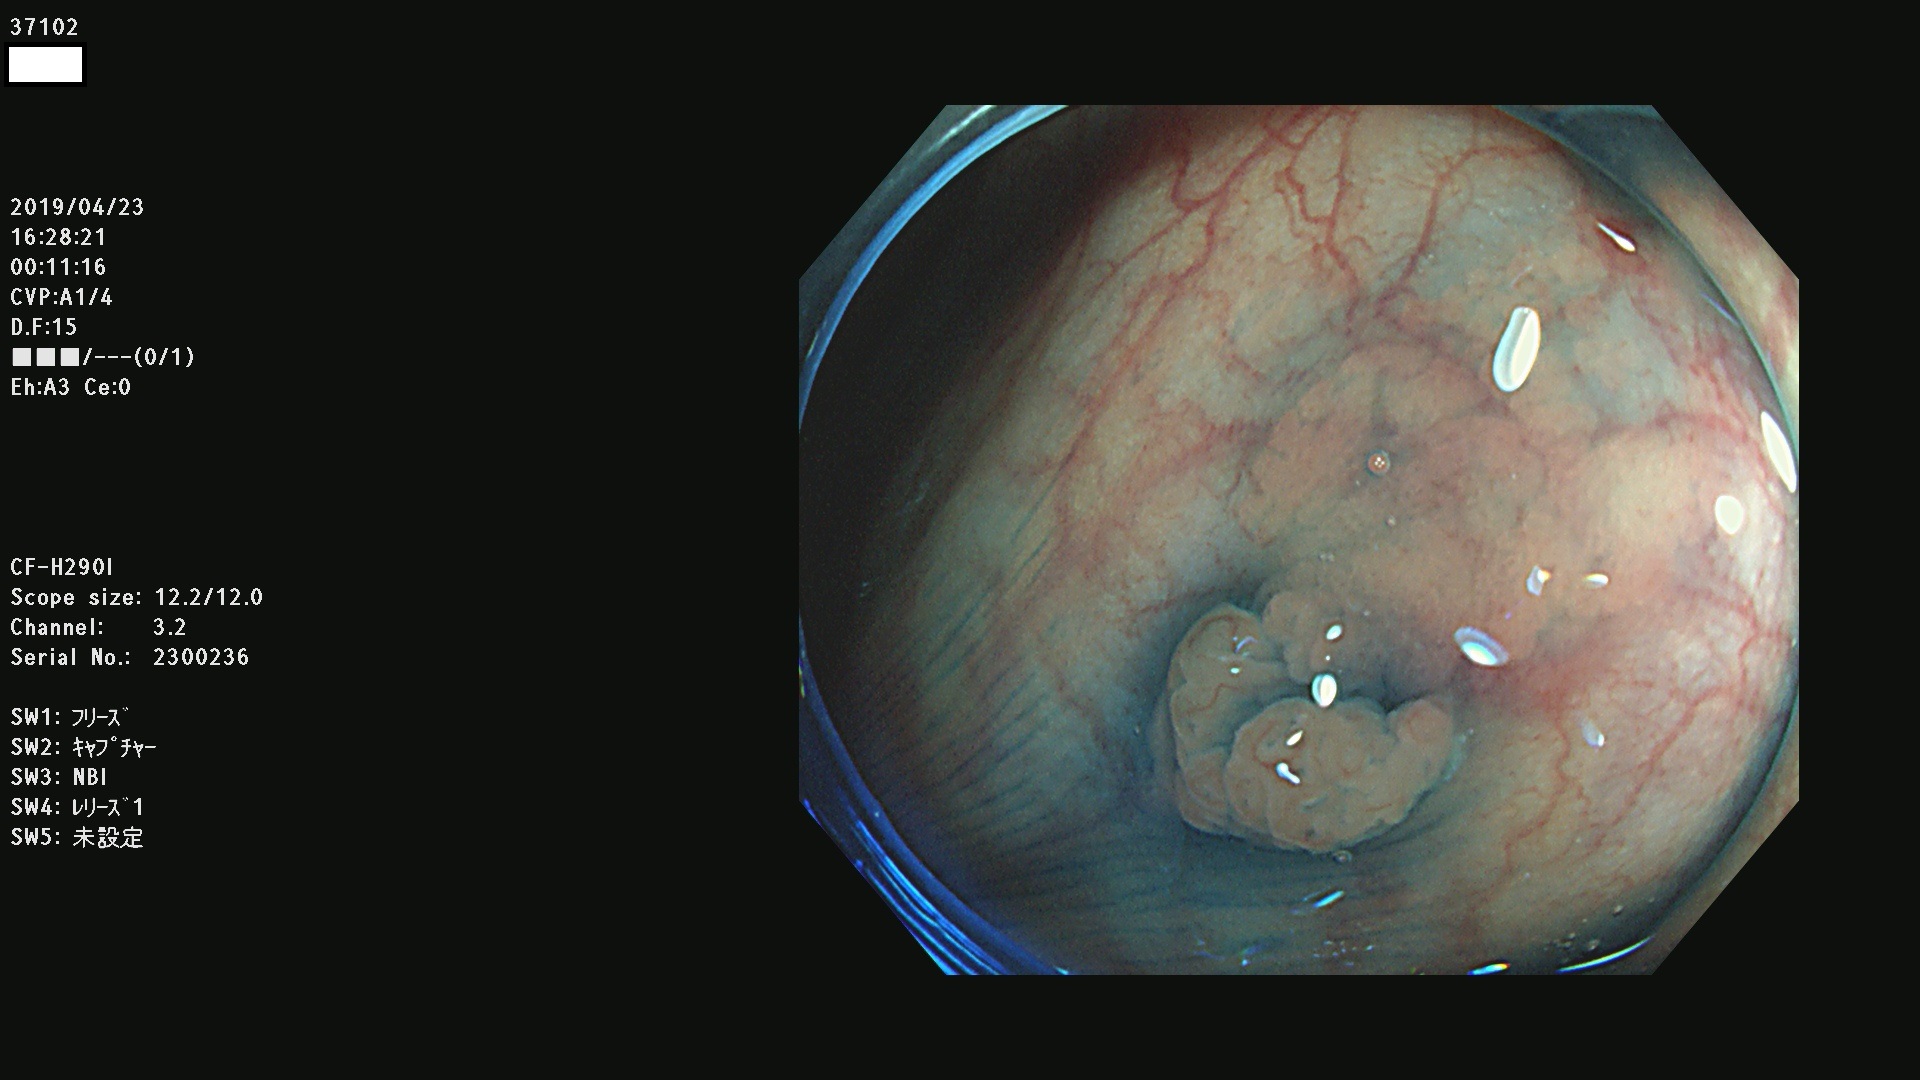

37100 37101 37102 37104 37106 37108 37110 37111 37112 37113 37115 37118(SSAPのみ) 37120 37122 37123 37124 37127(SSAPのみ) 37128(SSAPのみ) 37131 37132 37133 37134 37135 37139 37141 37142 37143 37144(SSAPのみ) 37145 37147(SSAPのみ) 37148 37149 37150 37153 37154 37157 37159 37161 37162 37163 37164 37165 37166 37167 37168 37169 37170 37171 37172 37173 37175(SSAPのみ) 37176 37177 37178 37180(SSAPのみ) 37181 37184 37185 37186 37187 37188 37189 37190 37192 37194 37197 37198

発見困難で危険性の高い平坦型病変(上記100名より抽出)